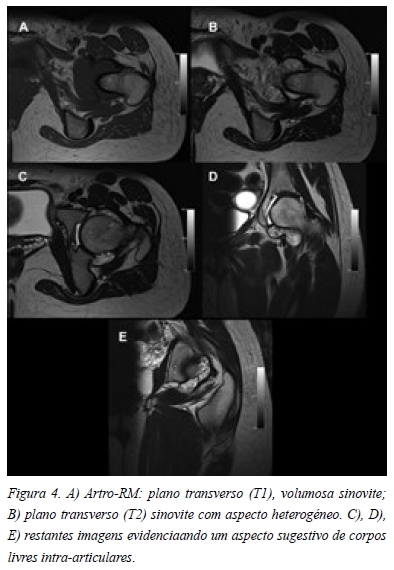

Na radiografia em incidência antero-posterior da bacia era possível observar uma flexão pélvica acentuada, o que condicionava uma falsa proeminência das espinhas isquiáticas e secundariamente uma retroversão focal (Figura 1 A). Também apresentava uma pequena perda de “offset” do colo à esquerda (Figura 1 A). Outros aspectos merecedores de atenção eram uma imagem de elevada densidade na fóvea (Figura 1 B) e o aumento da interlinha articular à esquerda (Figura 1 C). Na incidência de “cross table lateral” da anca esquerda também era possível observar a perda de “offset” do colo, apresentando um ângulo alpha de 69,3º (Figura 2). Nenhuma das incidências apresentava imagens características de condromatose sinovial. A paciente também trazia uma TC que revelava um “herniation pit” provavelmente relacionado com o conflito femoro-acetabular tipo CAM (Figura 3 A) e duas imagens invulgares na fóvea, compatíveis com corpos livres, mas sem origem identificável (Figura 3 B). A artro-RM apresentava uma volumosa sinovite na ponderação em T1 (Figura 4 A) e um aspecto heterogéneo em T2 (Figura 4 B), que se mantinham nos restantes cortes e que poderiam ser sugestivos de corpos livres (Figura 4 C, D, E). Sem outras imagens sugestivas de lesão labral ou cartilagínea.